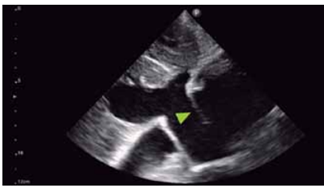

Assinale a alternativa correta em relação ao achado indicado pela seta na imagem a seguir.

(Arquivo pessoal; imagem utilizada com autorização)